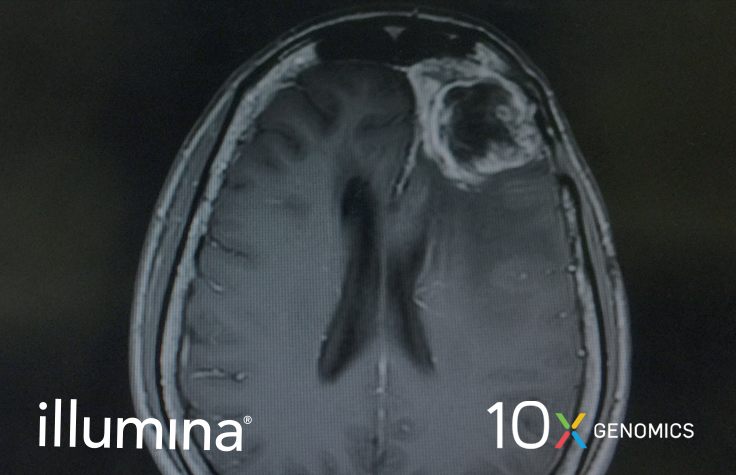

In this talk, Swetha Anandhan from the MD Anderson Cancer Center will highlight the use of single cell RNA-sequencing to identify a unique population of macrophages in glioblastoma multiforme that persists after treatment with immune checkpoint inhibitors.